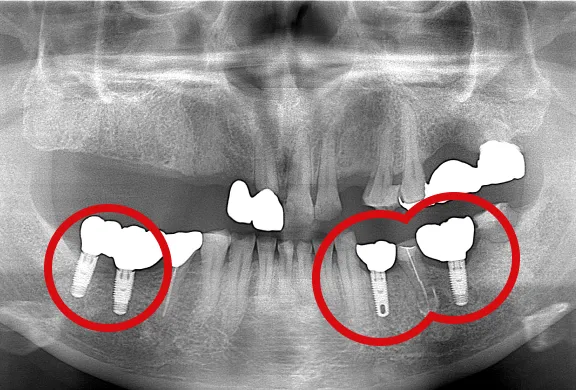

インプラントの埋め込み

上部構造の装着

パノラマ

歯間部のインプラント

(上部構造の装着)

-

(2本)

(2本、上部構造の装着)

上顎のインプラント

下顎のインプラント(4本)

下顎のインプラント(2本)